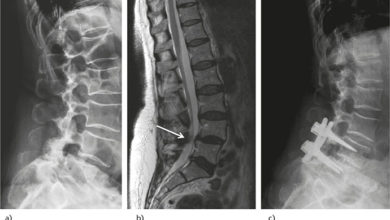

Omurga ve Dar Kanal Tedavisi

Omurilik kanalındaki kemik yapılarının, ligamenlerin kalınlaşması veya disk dokusunun bozulması gibi nedenlere bağlı olarak omurga kanalının daralmasıdır. Dar spinal kanal…